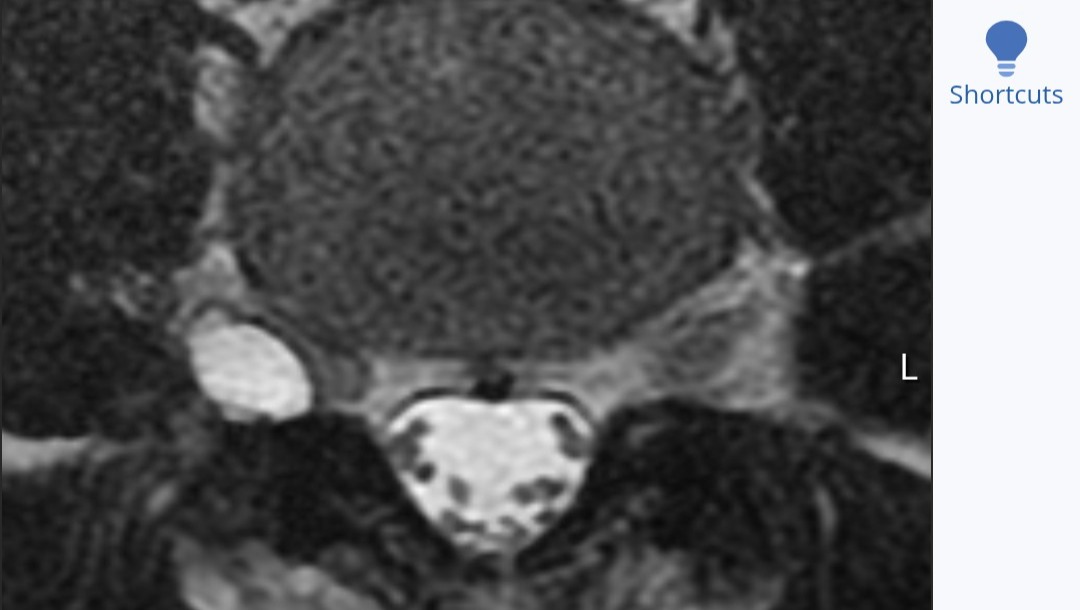

Here is the MRI of the growth from two views. As you can see it's right on the spine itself pushing on the nerves simulating a ruptured disk.